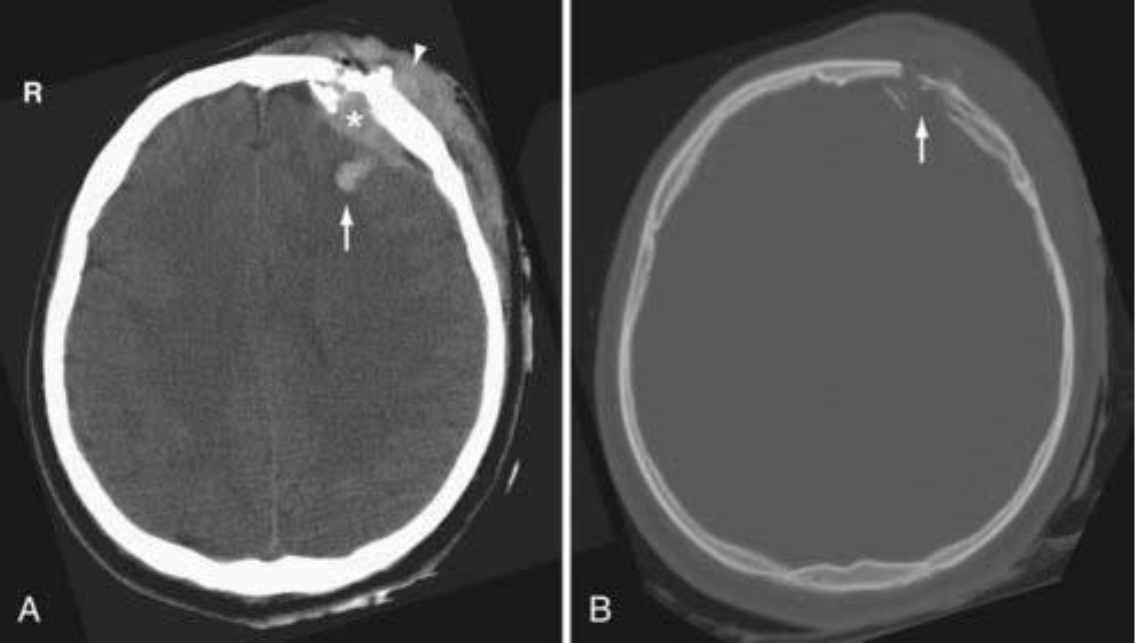

硬腦膜上出血 (Extradural haemorrhage, EDH)

臨床表現

• 噁心和嘔吐

• 意識改變

• 同側瞳孔擴張

• 清醒間隔 (Lucid interval)

• 僅 15-20% 患者出現典型的清醒間隔後昏迷復發

• 50% 患者並無初始意識喪失 (Initial loss of consciousness)

解剖與病因

• 最常見部位: 顳外側區域 (Lateral temporal)

• 血管來源: 中腦膜動脈 (Middle meningeal artery) 撕裂